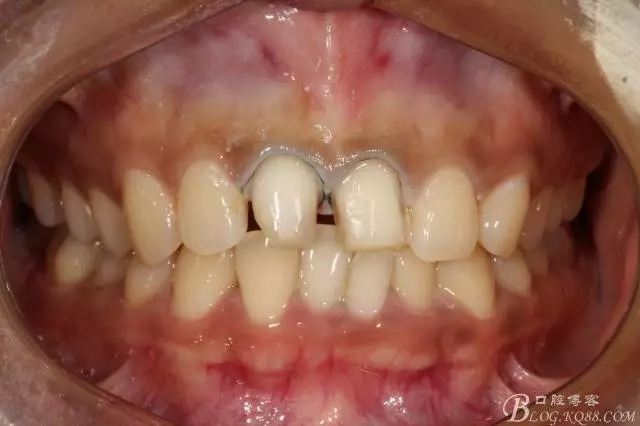

2016.1復(fù)查情況很不好,再次建議做瓷貼面并告知各自優(yōu)缺點(diǎn)。這回患者同意并選擇鑄瓷貼面。

11扭轉(zhuǎn)明顯,擔(dān)心備牙過多,所以選取了一個(gè)模型,在石膏模型上先試備后,感覺還行。

備牙后11(因扭轉(zhuǎn)制牙有點(diǎn)多,還是露牙本質(zhì)了)